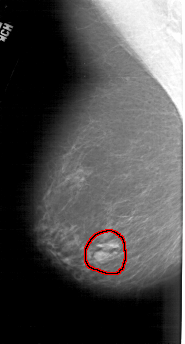

A_1942_1.LEFT_MLO

FILE: A_1942_1.LEFT_MLO.OVERLAY

TOTAL_ABNORMALITIES 1

ABNORMALITY 1

LESION_TYPE MASS SHAPE LOBULATED MARGINS ILL_DEFINED

ASSESSMENT 4

SUBTLETY 5

PATHOLOGY BENIGN

TOTAL_OUTLINES 1

BOUNDARY

LEFT_MLO LINES 5146 PIXELS_PER_LINE 2761 BITS_PER_PIXEL 12 RESOLUTION 43.5 OVERLAY